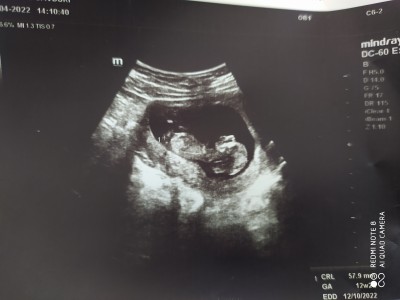

Burada 12+3 günlük falan şuan 14+3 olduk doktor tahminde bulundu ama net birşey demedi. Sizin fikrinizi merak ettim .

Anlamamda ilk aklıma gelen erkek oldu ☺️☺️ aklıma geleni söyledim sadece cinsiyetini öğrendikten snra bana söyler misiniz ☺️☺️

Canım ben 18. haftanın sonuna kadar öğrenememiştim hiç tahminde falan da bulunmadı doktor o zamana kadar doktor bir tahminde bulunsaydı burada sormazdım içimden erkek geçti hayırlı evlat olsun